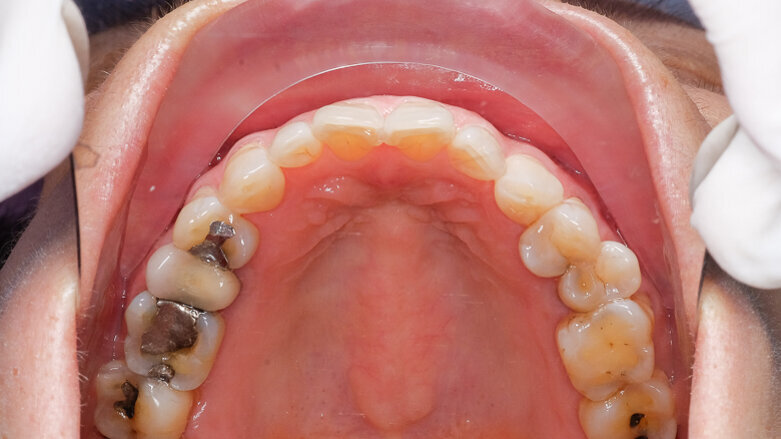

Practices will now be required to use separators and be prohibited from flushing waste amalgam, such as from traps or filters, down drains. The regulation also prohibits the use of bleach or chlorine-containing cleaners that may lead to the dissolution of solid mercury when cleaning chairside traps and vacuum lines. In a bid to reduce paperwork for dentists, the new rule will require a one-time compliance report to be filled out by all practices, regardless of whether they place or remove amalgam.

Although less than 1 percent of mercury released into the environment from man-made sources comes from dentistry, the ADA has encouraged dental offices to follow its best management practices for amalgam waste. In 2009, the association amended its best management practices to include the use of amalgam separators that comply with ANSI/ADA Standard No. 108 for Amalgam Separators, which takes into consideration the standards developed by the International Organization for Standardization, a worldwide federation of national standards bodies.

The new rule exempts dentists who practice in oral pathology, oral and maxillofacial radiology, oral and maxillofacial surgery, orthodontics, periodontics and prosthodontics. The regulation also excludes dentists who do not place amalgam and only remove amalgam in unplanned or emergency situations (estimated at less than 5 percent of removals) and mobile dental units. Dentists who already have separators are grandfathered for ten years.